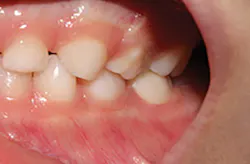

The steps for preparation and cementation were as follows. First, local anesthesia was delivered. Second, isolation was achieved with an isolation system (Isodry). Third, preparation steps were undertaken: Occlusal preparation was completed using a high-speed handpiece with copious amounts of water and a coarse, long-tapered diamond bur (NuSmile) to achieve an occlusal reduction of 1.5–2 mm. Circumferential reduction of approximately 15–20% was carried out using the same bur. In order to visualize the completeness and evenness of the preparation, a full circumferential reduction supragingivally was completed at this stage. A subgingival preparation was again completed using a high-speed handpiece with copious water and a finer, more tapered diamond bur (NuSmile). As required, a full subgingival reduction to approximately 1.5 mm depth was achieved, ensuring no ledges and a smooth featheredge margin (figure 2). It was essential that the crown fit passively and be able to be seated completely unencumbered. In order to ensure fit and occlusion and to prevent contamination of the zirconia crown to be cemented, a Try-In crown (NuSmile) was used (figure 3). Refinements to the preparation to facilitate fit and occlusion were done at this point.

Figure 2: Full subgingival reduction to approximately 1.5 mm depth